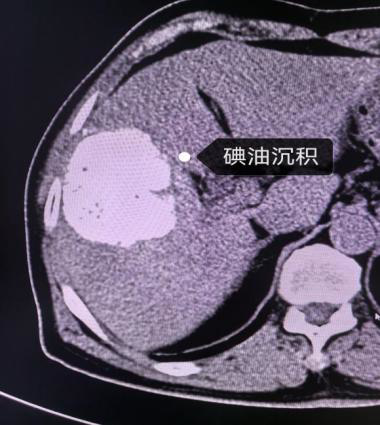

(二)肿瘤治疗

在肿瘤治疗领域,介入同样表现非凡。它可以将化疗药物直接输送到肿瘤部位,提高局部药物浓度,增强治疗效果,同时减少对全身的副作用。又或是通过血管栓塞,切断肿瘤的营养供应,抑制肿瘤生长,为患者带来新的希望。

肝Ca介入治疗